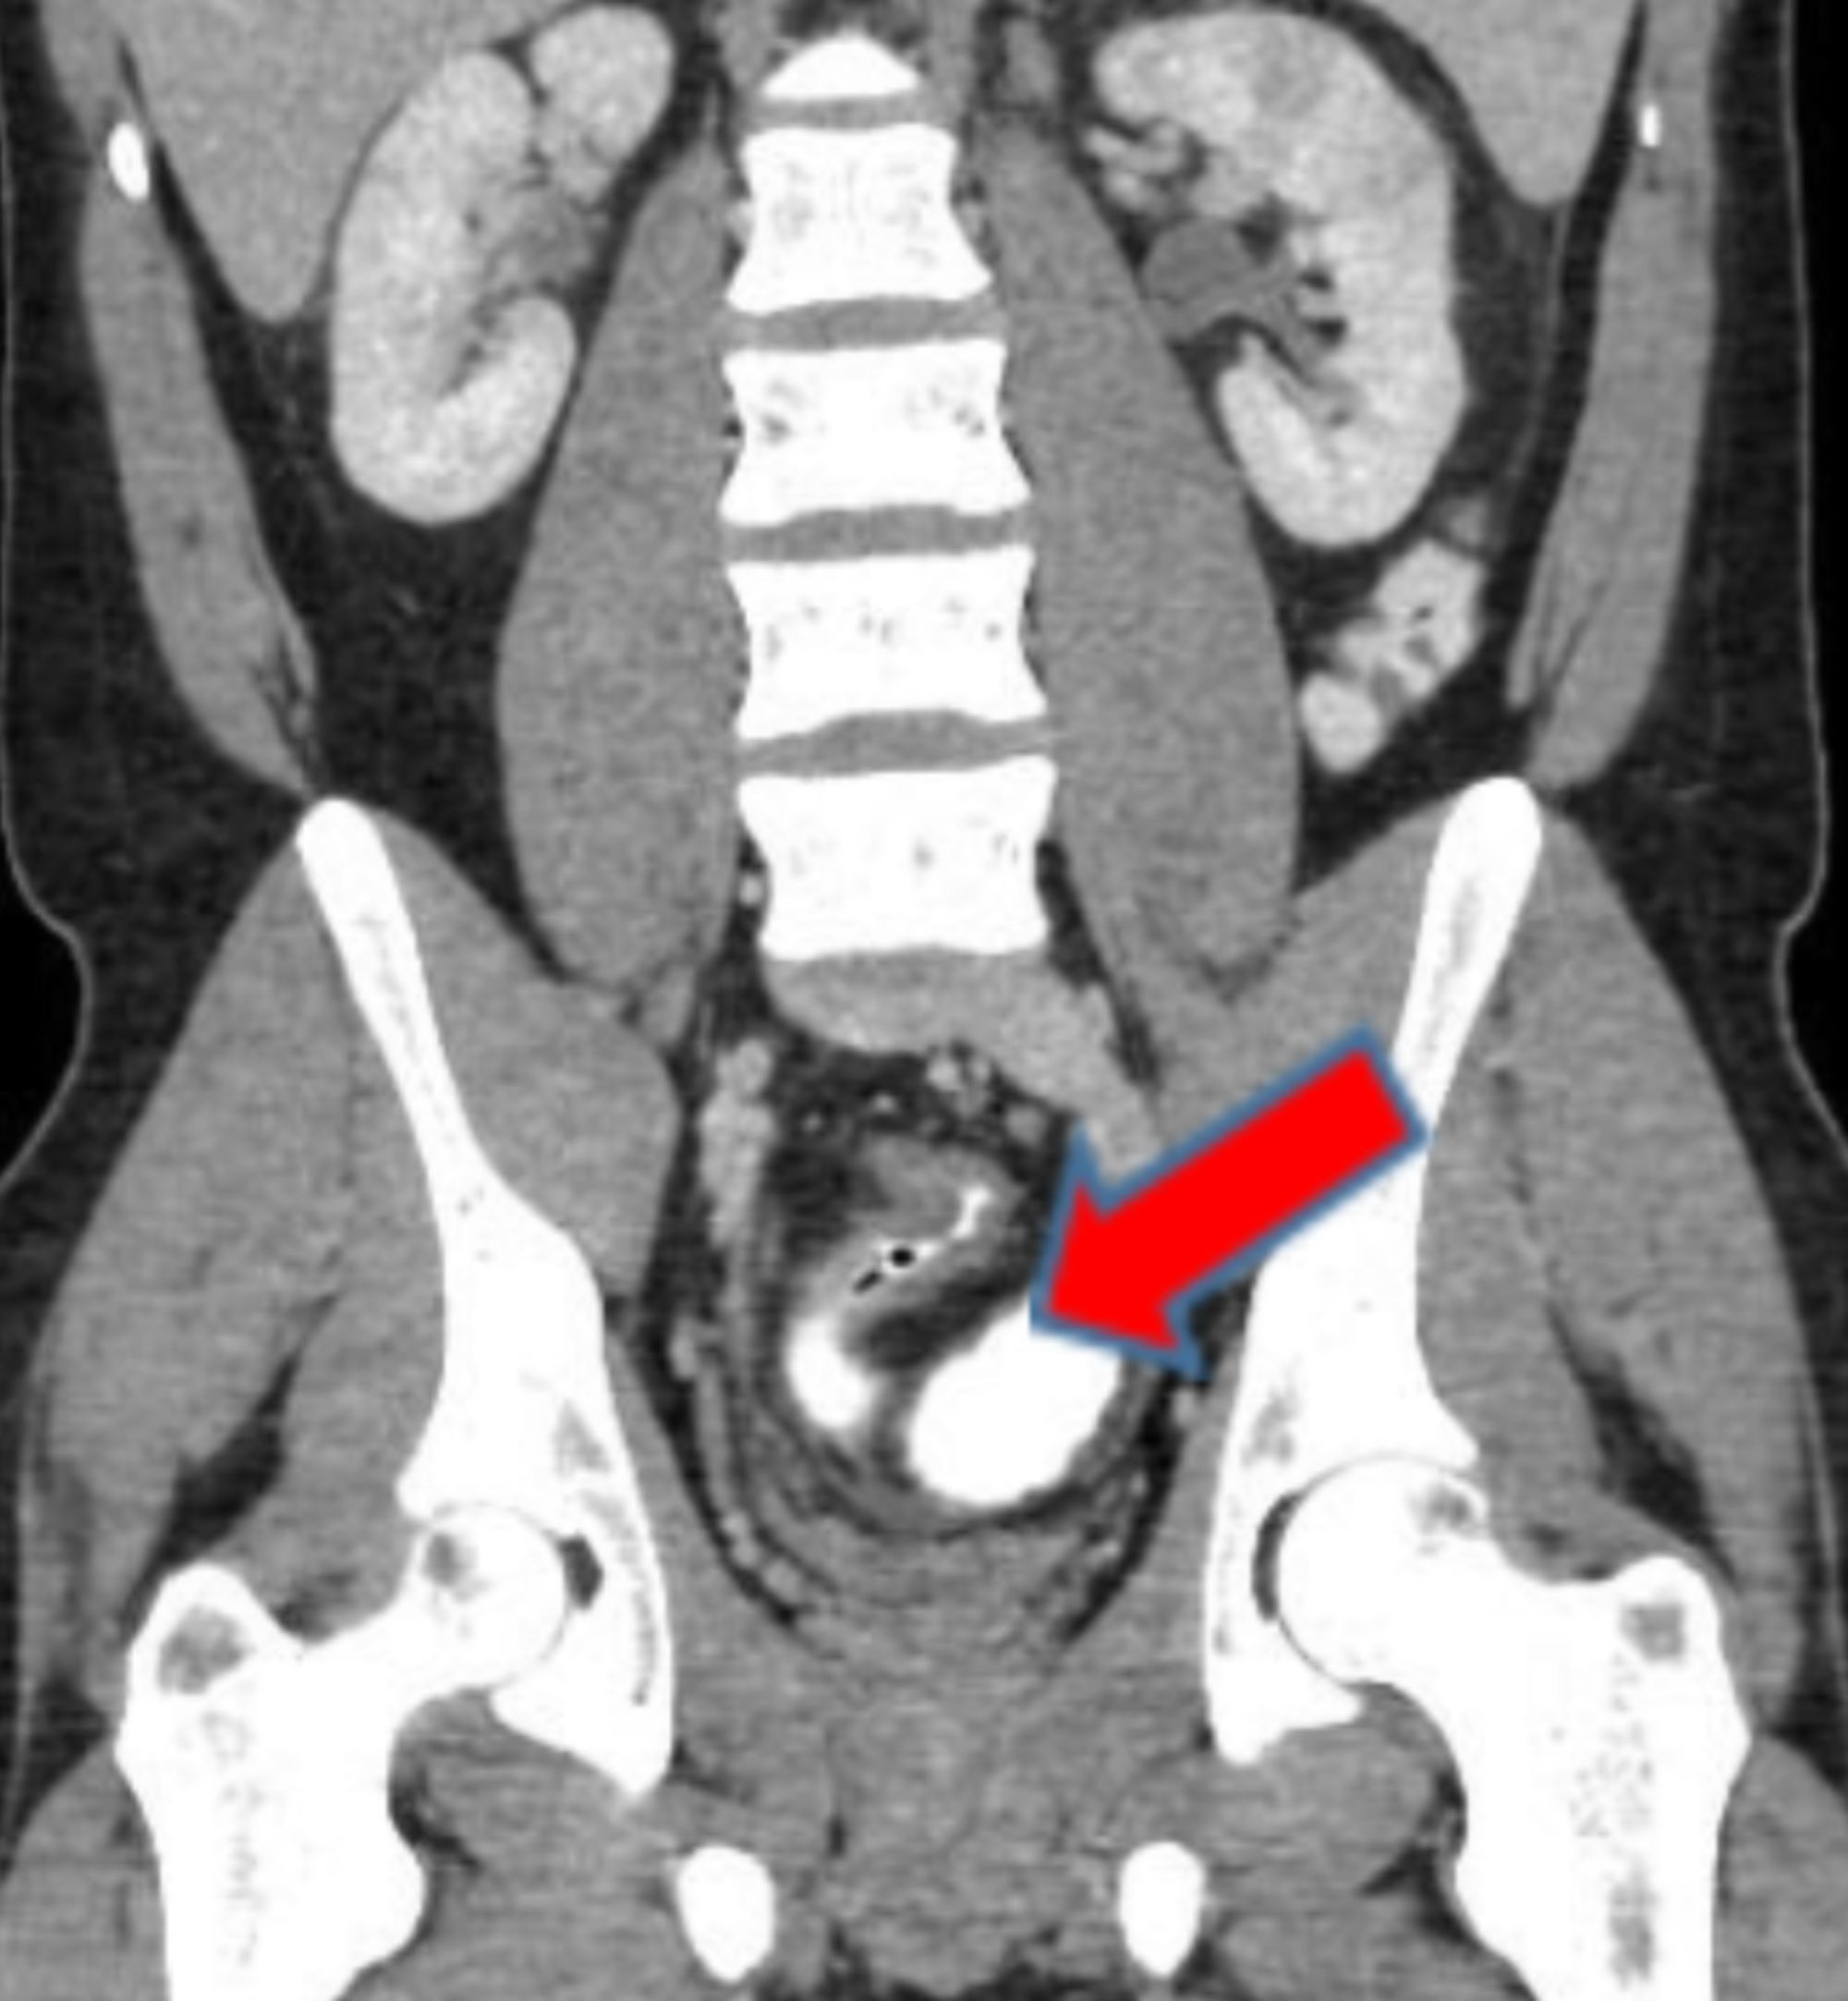

Urinary complications in Crohn’s disease and ulcerative colitis

(PDF) Crohn’s Disease and Urinary Manifestations A Crohn’s Intestinal Crohn's Disease Urine People diagnosed with crohn’s disease have a higher risk of developing kidney stones in the urinary tract than those without crohn’s, including those with ulcerative colitis. In people with crohn’s disease, hydronephrosis often occurs in the right kidney, close to the terminal ileum. Cystitis was the most common. Increased urination is one possible symptom of. Inflammatory bowel disease (ibd) is. Crohn's Disease Urine.

Crohn's disease. Contrastenhanced CT scan shows distal ileal loops Crohn's Disease Urine Ulcerative colitis (uc) and crohn disease (cd). People with ulcerative colitis are more likely to develop kidney stones — hard deposits of salts and minerals in the kidneys. Increased urination is one possible symptom of. Inflammatory bowel disease (ibd) is comprised of two major disorders: Cystitis was the most common. Crohn’s disease is a lifelong condition that causes inflammation in. Crohn's Disease Urine.